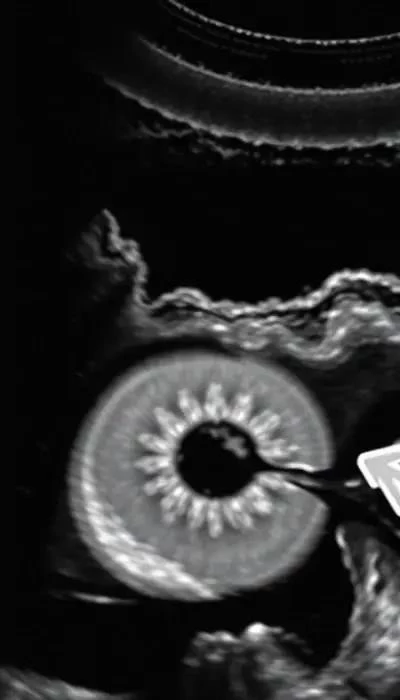

Своевременная диагностика кист яичников имеет решающее значение. Гинекологический осмотр, ультразвуковое исследование (УЗИ) и анализ крови на гормоны позволяют определить наличие кисты, ее размер и структуру. В некоторых случаях могут потребоваться дополнительные методы исследования, такие как компьютерная томография (КТ) или магнитно-резонансная томография (МРТ). Помните, что при любых подозрениях на кисту яичника необходимо обратиться к врачу-гинекологу для получения квалифицированной консультации и назначения адекватного лечения. Киста яичника: причины, симптомы и признаки требуют внимательного отношения к своему здоровью.

Яичники – это парные женские половые железы, расположенные по обеим сторонам от матки. Они выполняют две основные функции: выработку яйцеклеток (оогенез) и синтез половых гормонов – эстрогенов и прогестерона. Строение яичников достаточно сложное. Они покрыты эпителием и состоят из двух основных слоев: коркового вещества и мозгового вещества.

Корковое вещество содержит фолликулы, в которых созревают яйцеклетки. Фолликул – это структура, состоящая из яйцеклетки и окружающих ее клеток. В течение менструального цикла несколько фолликулов начинают расти, но обычно только один из них достигает зрелости и выходит из яичника во время овуляции. Мозговое вещество содержит кровеносные сосуды, нервы и лимфатические сосуды, обеспечивающие питание и иннервацию яичника.